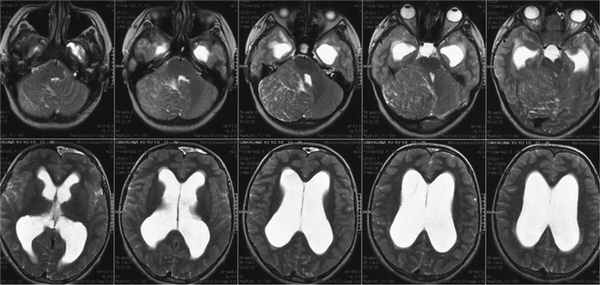

Магнитно-резонансная томография

Утолщение "листовидной структуры" мозжечка с исчерченым/тигровым паттерном.

- T1: гипоинтенсивный МР сигнал [2]

- T2: гиперинтенсивный сигнал за счет кортикальной исчерченности [1]

В НИИ нейрохирургии поступила больная С., 17 лет. За несколько месяцев до госпитализации стала отмечать шаткость при ходьбе, периодическую головную боль. В неврологическом статусе выявлялась окклюзионная, общемозговая, а также выраженная мозжечковая симптоматика. Из анамнеза известно, что в 2002 г. была произведена струмэктомия по поводу опухоли щитовидной железы, в связи с чем принимала L-тироксин. С 2006 г. наблюдалась по поводу макроцефалии. При проведении МРТ головного мозга выявлены объемное образование правой гемисферы мозжечка и окклюзионная гидроцефалия с признаками перивентрикулярного отека (рис. 1). По результатам КТ в сосудистом режиме сделано предположение о наличии артериовенозной мальформации правой гемисферы мозжечка (рис. 2). Для уточнения диагноза проведена церебральная ангиография, в ходе которой диагноз артериовенозной мальформации не подтвердился (рис. 3).

Рис. 1. МРТ в режиме Т2. Гиперплазия правого полушария мозжечка. Окклюзионная гидроцефалия. Рис. 2. СКТ-ангиография. Определяется расширенная окципитальная вена, которая ошибочно была принята за артериовенозную мальформацию. Рис. 3. Правосторонняя вертебральная ангиография. Боковая (а) и прямая (б) проекция. Отмечается некоторое смещение вверх и медиально от начального отрезка правой задней мозговой артерии, смещение за среднюю линию правой задней нижней мозжечковой артерии. Каудальная петля ее опущена в позвоночный канал. Широкое расположение полушарных ветвей правой верхней мозжечковой артерии.

В НИИ нейрохирургии пациентке была выполнена повторная МРТ, подтвердившая ранее выявленную патологию (рис. 4).

Рис. 4. На МРТ головного мозга в режиме Т2 в аксиальной проекции — «пестрый» рисунок правого полушария мозжечка с увеличением его размеров. IV желудочек смещен влево, сужен. III и боковые желудочки расширены.

При ретроспективном анализе снимков, выполненных в 2006 г. по поводу макроцефалии, в правой гемисфере мозжечка установлено объемное образование небольшого размера, практически не отличающееся от вещества мозжечка (рис. 5).

Рис. 5. МРТ головного мозга в аксиальной проекции, режим Т2 (2006 г.).

(а) МРТ, Т1 -ВИ, аксиальный срез: у женщины 5 7 лет с головными болями в правом полушарии и черве мозжечка определяется умеренно гипоинтенсивное объемное образование.

(б) МРТ, Т2-ВИ:утойже пациентки определяются гиперинтенсивность образования и его полосатая гириформная конфигурация.5. Рекомендации по визуализации:

о При контрастировании образования необходимо внимательное проведение дифференциальной диагностики(а) MPT, FLAIR, аксиальный срез: у той же пациентки образование имеет гиперинтенсивный сигнал (по сравнению с нормальным левым полушарием мозжечка). Сигнал от нескольких кист внутри образования, содержащих жидкость, полностью подавлен.

(б) МРТ, Т2-ВИ, корональный срез: у образования определяется полосатая «тигровая» структура. Листки пораженного полушария мозжечка расширены по сравнению с нормальным левым полушарием. (а) МРТ, постконтрастное Т1-ВИ: у той же пациентки отмечается отсутствие контрастирования образования, но видны точечные и линейные зоны контрастирования, представляющие собой крупные сосуды.